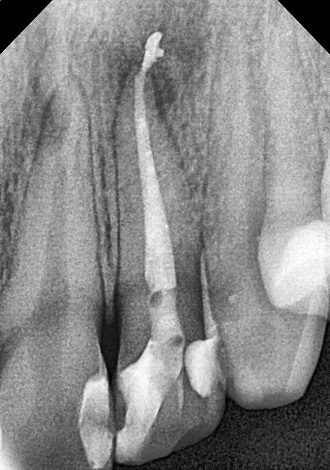

Пломбування кореневих каналів.

Якісно запломбовані кореневі канали є основою

довговічності. Тому очищення і пломбування кореневих каналів в «Домі Стоматології»

приділяється особлива увага! Після пломбування кореневих каналів проводиться

контроль якості пломбування за допомогою знімка.